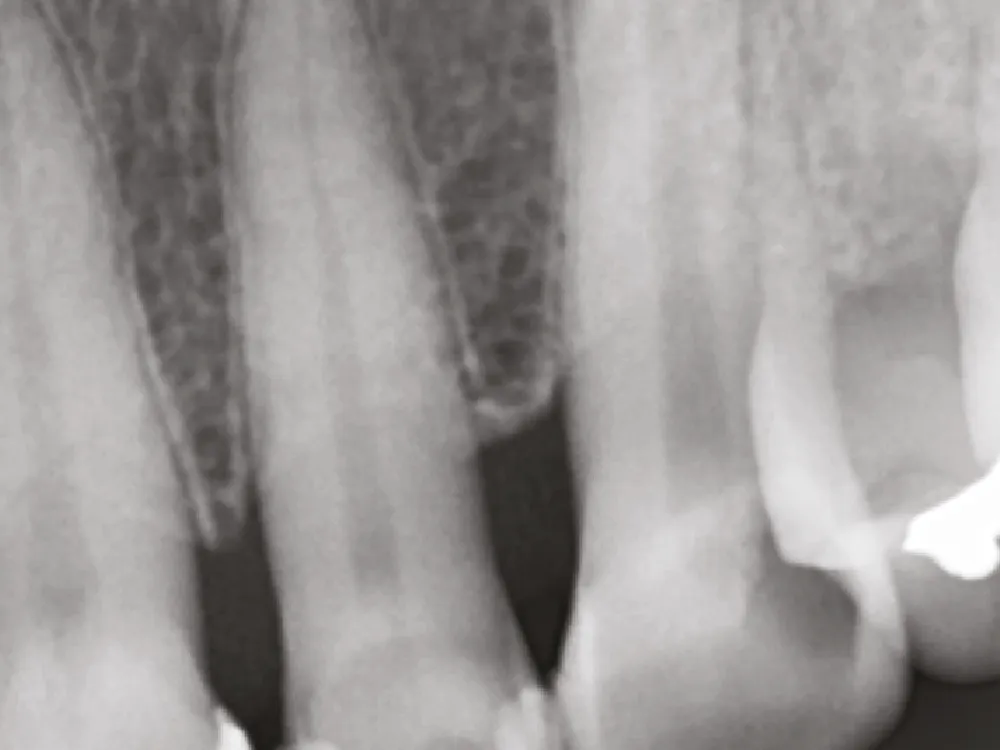

Excellente radiopacité

Le spécimen montre une excellente radiopacité à 10,81 mm d'aluminium.